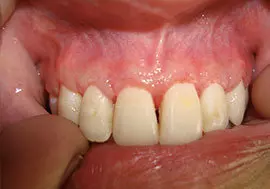

Some symptoms of periodontitis includes bleeding gums, bad breath, increased sensitivity to heat & cold and in later stages pain, swelling, pus discharge & mobility of teeth.

Gingival recession, resulting in apparent lengthening of teeth

Deep pockets between the teeth and the gums